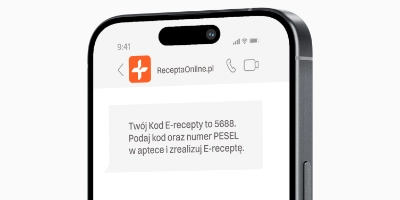

- Możesz uzyskać e-receptę i kod SMS do realizacji